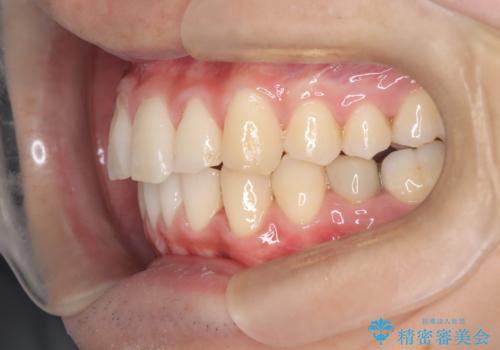

- 凸凹を治したいと来院された患者様です。

インビザラインにて、遠心移動を行いながら綺麗に配列することができました。